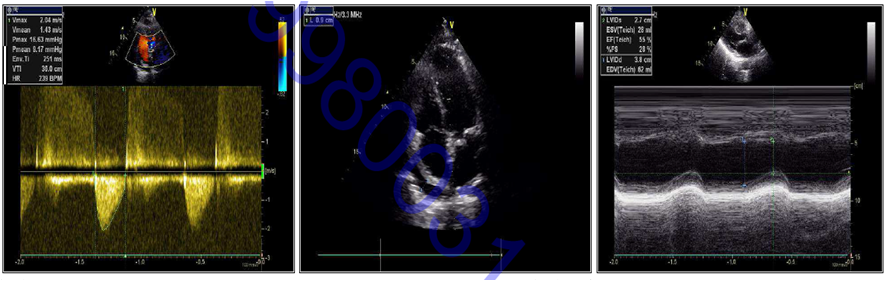

心脏超声

➤ LA33mm LV38mm IVS7mm LVPW7mm EF55%

➤ 心包局部增厚,右房顶少量心包积液,三尖瓣少中量反流,主动脉瓣轻微狭窄并少量反流